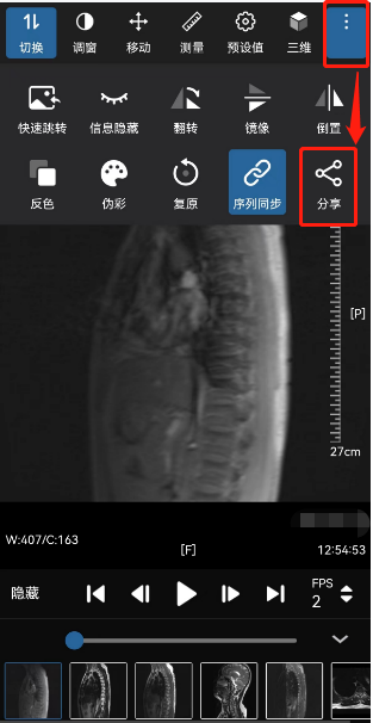

5.在图像查看界面按步骤点击“分享”功能键,可生成图像调阅二维码,扫码即可查看图像。